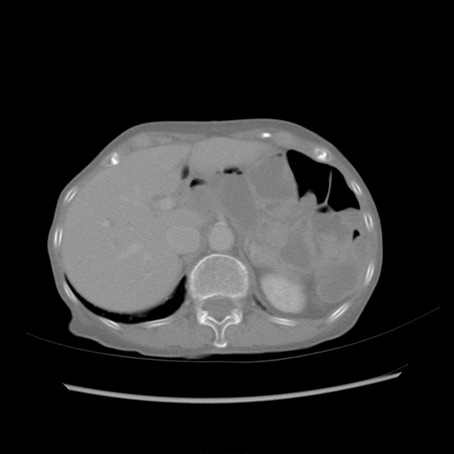

症例25(横断像)

【症例】80歳代女性

【主訴】胸のつかえ感

【現病歴】約9時間前に食後から胸のつかえた感じあり、嘔吐あり、来院。

【既往歴】胃癌(全摘)、胆摘、虫垂炎

【身体所見】心窩部に圧痛あり、反跳痛なし。

【データ】WBC 5700、CRP 0.05